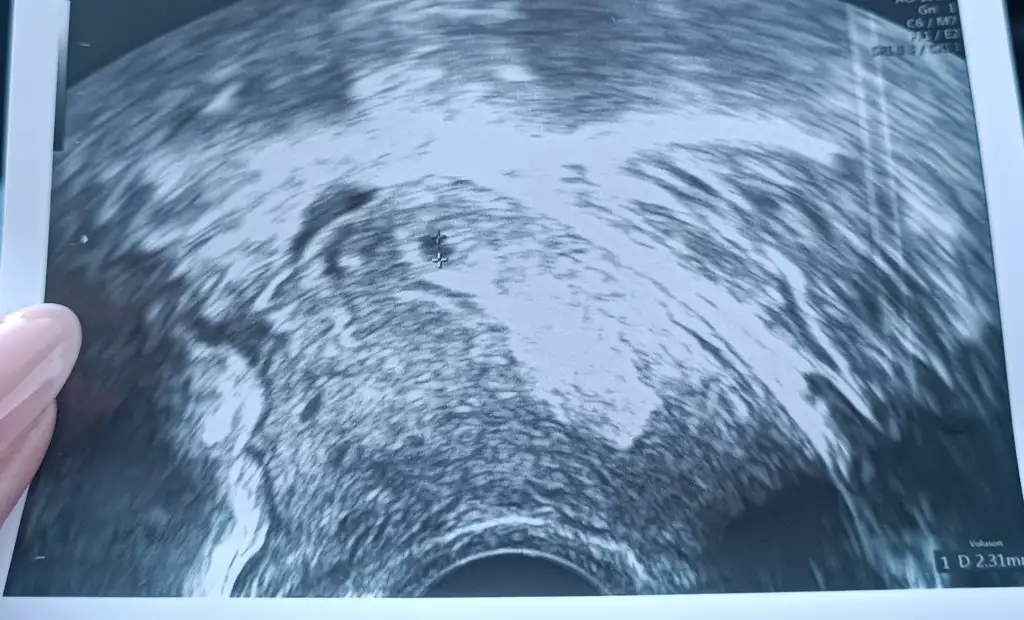

Sanırım iyiyim diye kendime cok yuklendimHayırlı geceler bu süreçte inzivaya çekilmek en güzeliimkan dahilinde tabi ki iyice dinlenin inşallah yarın bişeyiniz kalmaz arada bir bana da ağrı oluyor

Kimsede bilmiyor gebe oldugumu

Yatabilsem agridan insallh gecer sabaha